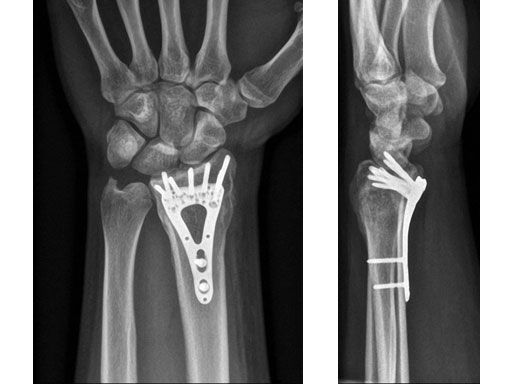

Fig 4ab X-rays 3 months postoperatively.